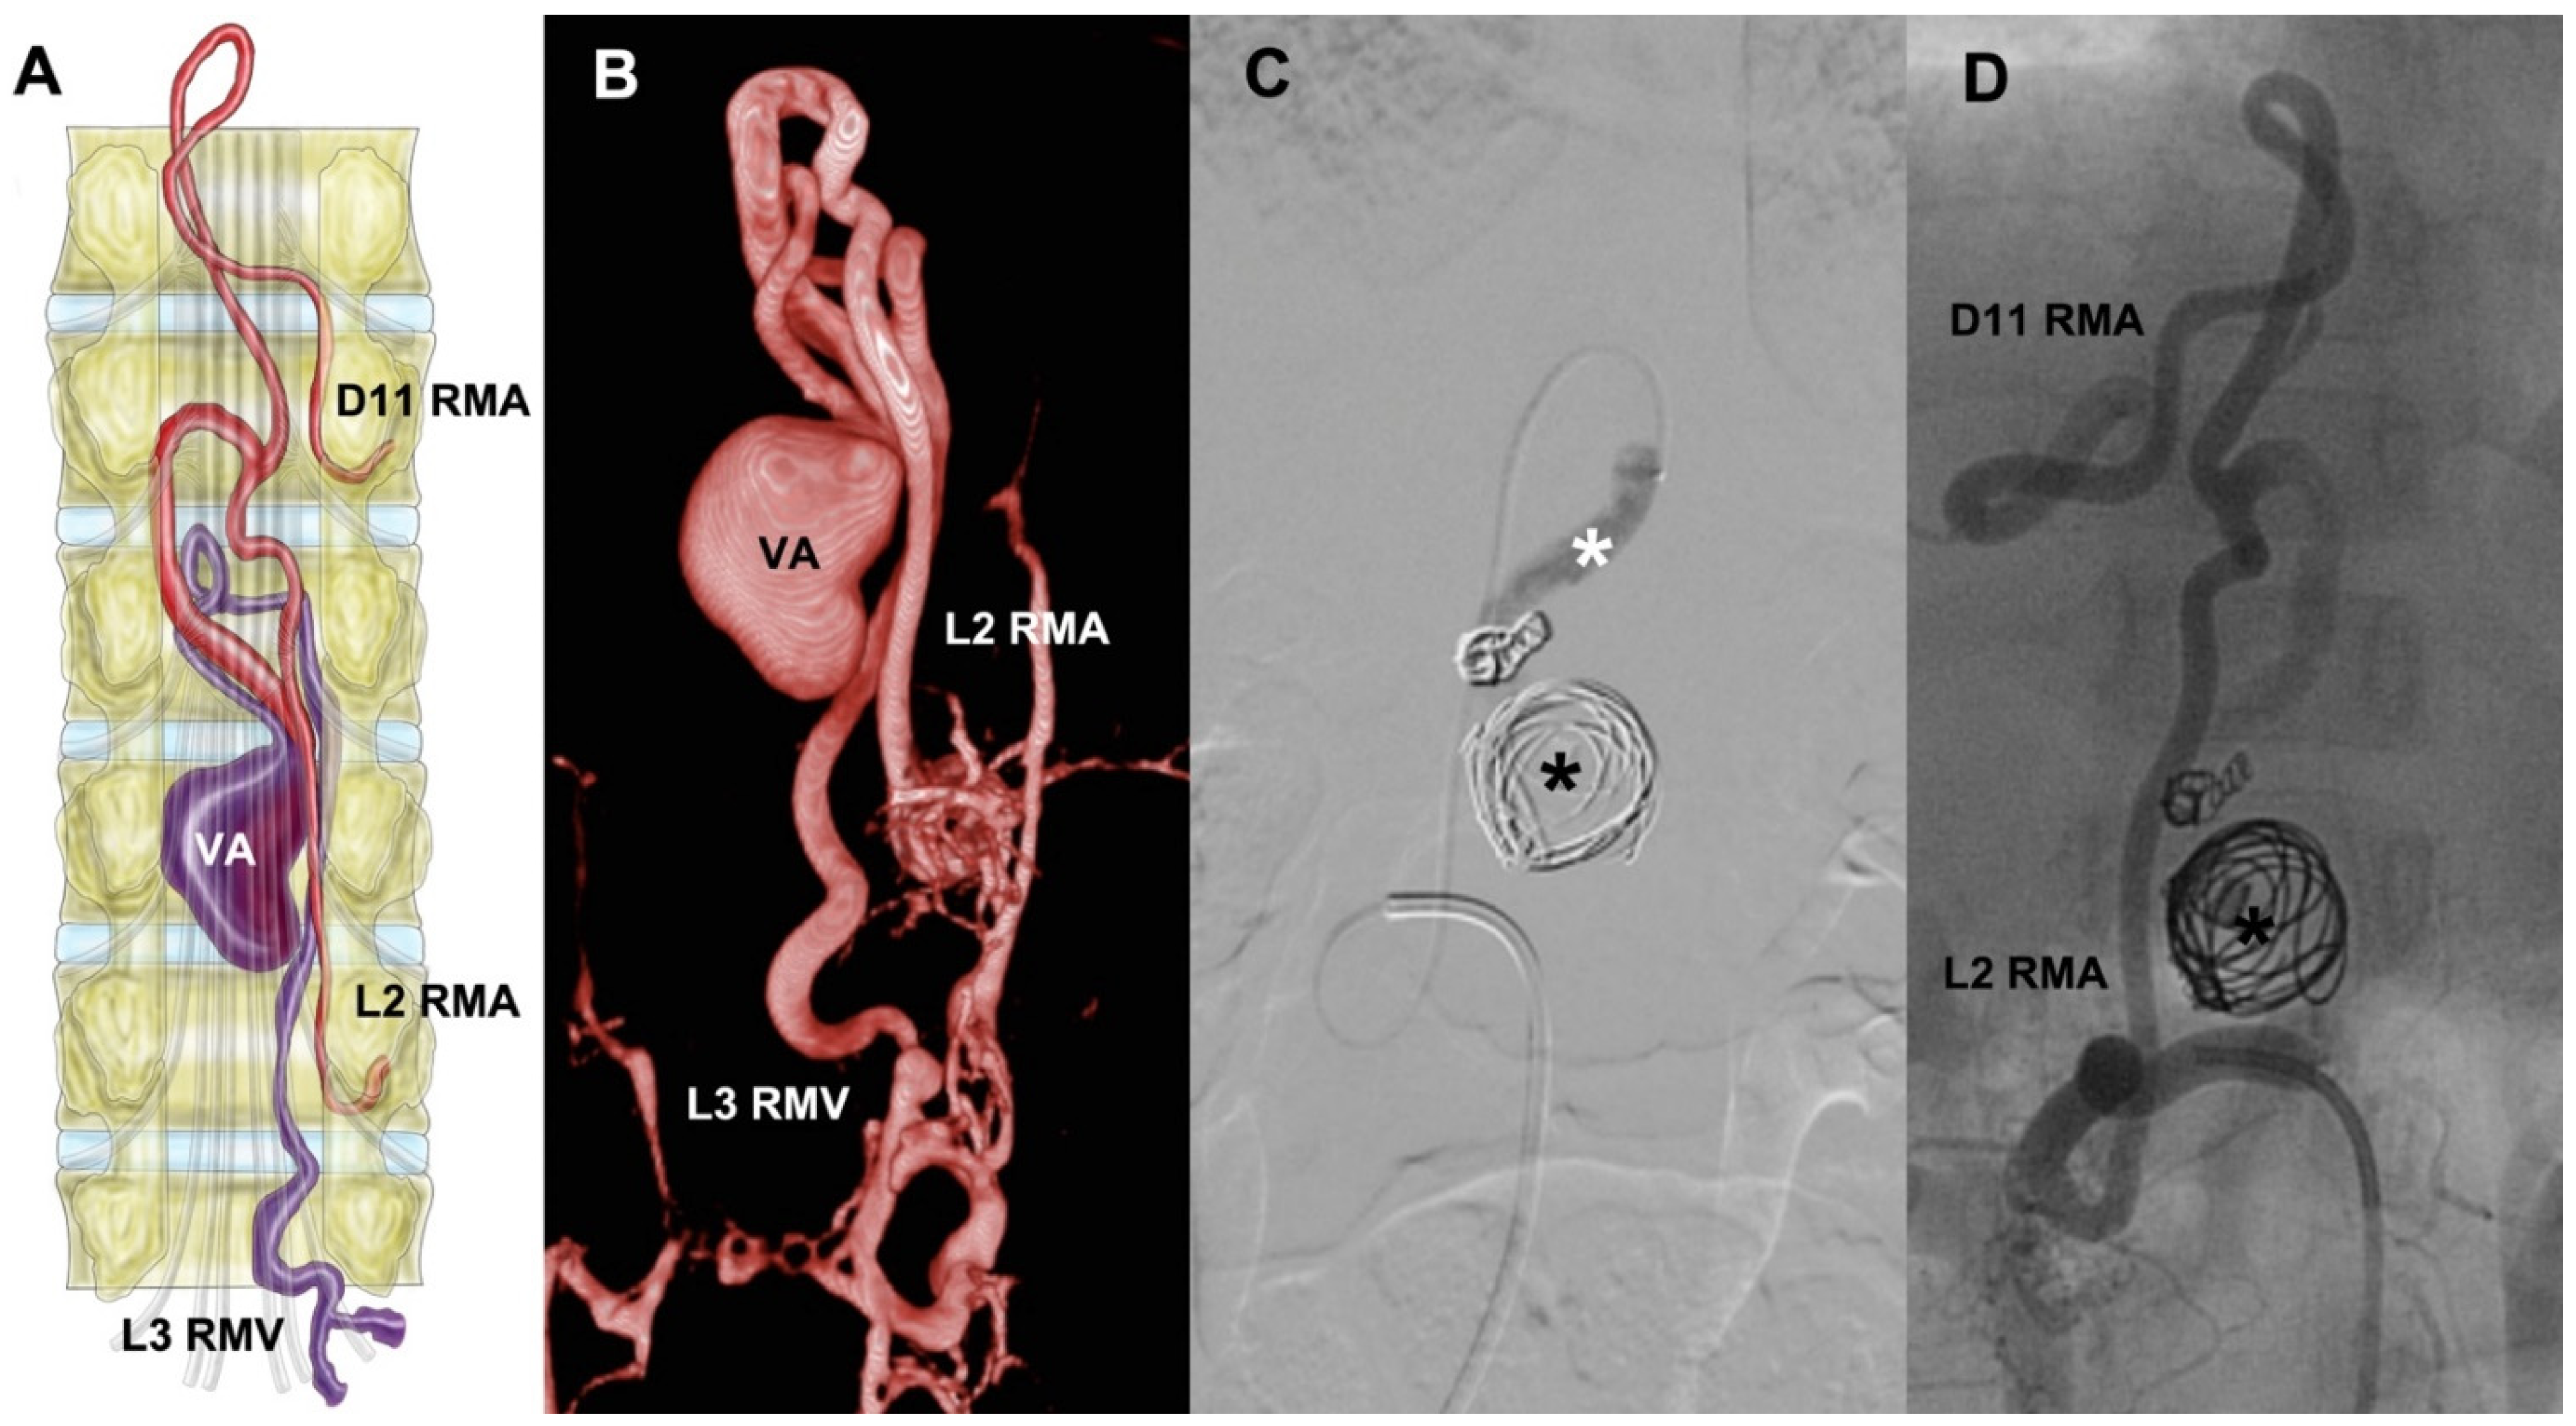

3.5.1. Case 4

A 3-year-old female with developmental delay and lumbar pain had undergone L1 laminectomy when she was 1 year old. At admission, she had paraparesis 4/5. sDSA showed a lesion with fistulous ostium at D12-L1, a venous aneurysm, afferents from right D11 and L2 radiculomedullary arteries, and venous drainage through the L3 radiculomedullary vein (Figure 1). The procedure was performed with a Rebar 18 microcatheter assisted with a Silver Speed 16 micro-guidewire. We achieved the catheterization of the sAVF. Then, we proceeded to embolization with coils, first MicroPlex 18 Cosmos (14 mm × 51 mm), then six HydroCoils, and finally we instilled Histoacryl. The angiographic control showed total occlusion of the vascular lesion.

Figure 1.

Depiction of a ventral sAVF at medullary cone schematized (A). It has two feeders at right D11 and L2 RMA, and then it shows a venous aneurysm followed by its drainage through L3 RMV. (B) The 3D sDSA reconstruction, followed by the embolization process and the exclusion of the lesion (C,D). RMA = radiculomedullary artery, RMV = radiculomedullary vein, VA = venous aneurysm, black asterisk = coils inside VA, white asterisk = Histoacryl at the sAVF. Illustrated by J. Lizana.